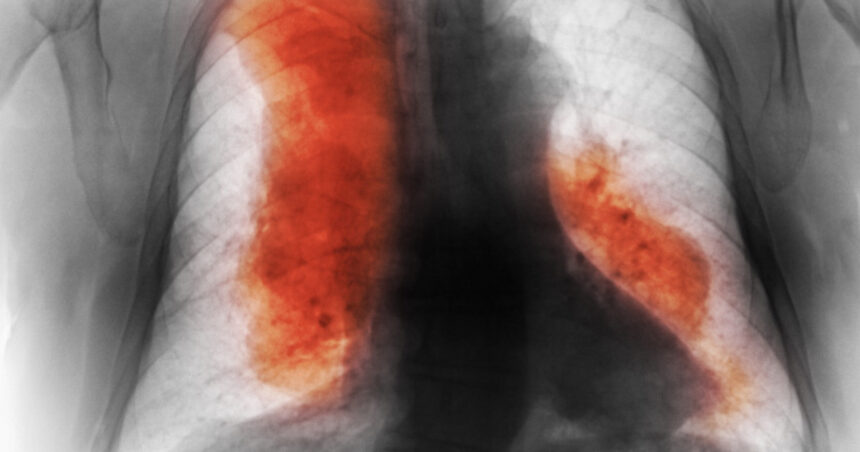

Numărul deceselor cauzate de cancer a crescut dramatic la nivel global în ultimele decenii și este estimat că va depăși 18,5 milioane până în 2050, conform unui studiu recent publicat în jurnalul științific The Lancet. Această evaluare, parte a studiului „Povara globală a bolilor”, sugerează că, în ciuda progreselor în tratamente, numărul cazurilor noi de cancer a crescut de peste două ori din 1990, atingând 18,5 milioane în 2023.

De asemenea, numărul deceselor cauzate de cancer a crescut cu 74%, ajungând la un total de 10,4 milioane. Studiul acoperă 204 de țări și 47 de tipuri de cancer, oferind estimări cu o marjă de incertitudine. Aceasta sugerează că, fără intervenții adecvate, numărul de cazuri noi ar putea crește cu 61% în următorii 25 de ani, atingând 30,5 milioane în 2050 și că decesele anuale ar putea crește cu aproape 75%, ajungând la 18,5 milioane.

Cercetătorii subliniază că majoritatea pacienților se află în țări cu venituri mici și medii, iar cancerul mamar este cel mai frecvent diagnosticat tip de cancer. În contrast, cancerele traheale, bronhice și pulmonare sunt cele mai frecvente cauze de deces. De asemenea, mai mult de 41% din decesele cauzate de cancer sunt atribuite unor factori de risc modificabili, precum fumatul, alimentația nesănătoasă și consumul excesiv de alcool.

Cercetătorii fac apel la îmbunătățirea prevenției prin diagnosticare precoce și tratamente eficiente, precum și la o creștere a finanțării pentru a reduce inegalitățile în accesul la îngrijiri medicale. Limitările studiului, cum ar fi lipsa unor date solide din anumite țări și impactul pandemiei de COVID-19, sunt recunoscute de autori, ceea ce face necesară o abordare atentă a acestor estimări.